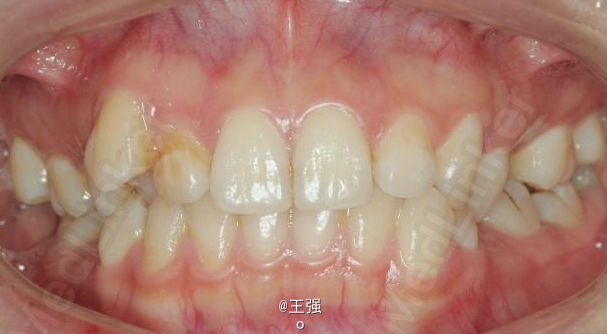

又一例不对称拔牙

牙弓狭窄,牙列拥挤

不对称拔牙